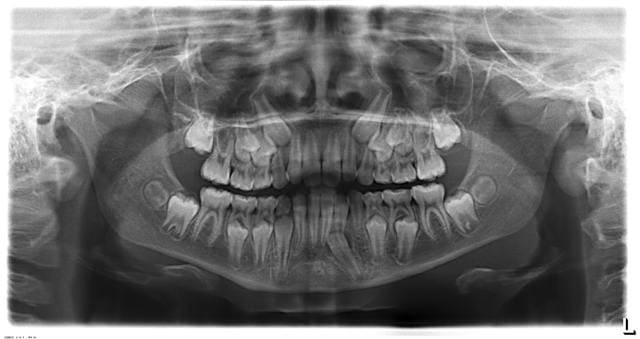

bonjour, pour mon premier sujet sur ce forum j'aurai besoin de vos avis concernant l'évolution de cette 33.

Sur ces deux radios à un an d'intervalle on voit bien que la malposition de 33 s'est aggravée, la palpation montre un site d'éruption en vestibulaire de 32.

Quelle solution s'offre à nous ?

P.S.: à la Rx., l'angulation des canines laisse supposer une constriction Post.

Le leeway est déjà perdu, le plan Post. tangent à la face distale de 75 n’est plus tangent à la face distale de 55, de m pour 85. je dirai qu’il manque 2 mm.

"Sur ces deux radios à un an d'intervalle on voit bien que la malposition de 33 s'est aggravée, la palpation montre un site d'éruption en vestibulaire de 32."

la situation s'est aggravée parce que tu bloques la croissance osseuse avec l'E.L.N.

Cette dent est en train d'évoluer vers l'inclusion.

Il est très fortement souhaitable de la tracter dès maintenant en distal, sans attendre.